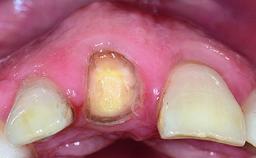

A healthy 28-year-old female patient presented for a consultation on treatment options to restore her upper right central incisor. At the clinical examination, the tooth responded to percussion and palpation. The gingiva was red and slightly swollen, with a mid-facial probing depth of 10 mm. The upper right lateral incisor showed no signs or symptoms, did not respond to exploration and percussion, and the vitality test was positive. The periapical radiograph revealed that tooth 11 had been endodontically treated, with no lesion evident at the apex. A small radiopaque calcified structure surrounded by a narrow radiolucent zone (3 × 3 mm) was present at the apex of tooth 12.

Bone Volume Deficient horizontally, allowing simultaneous augumentation